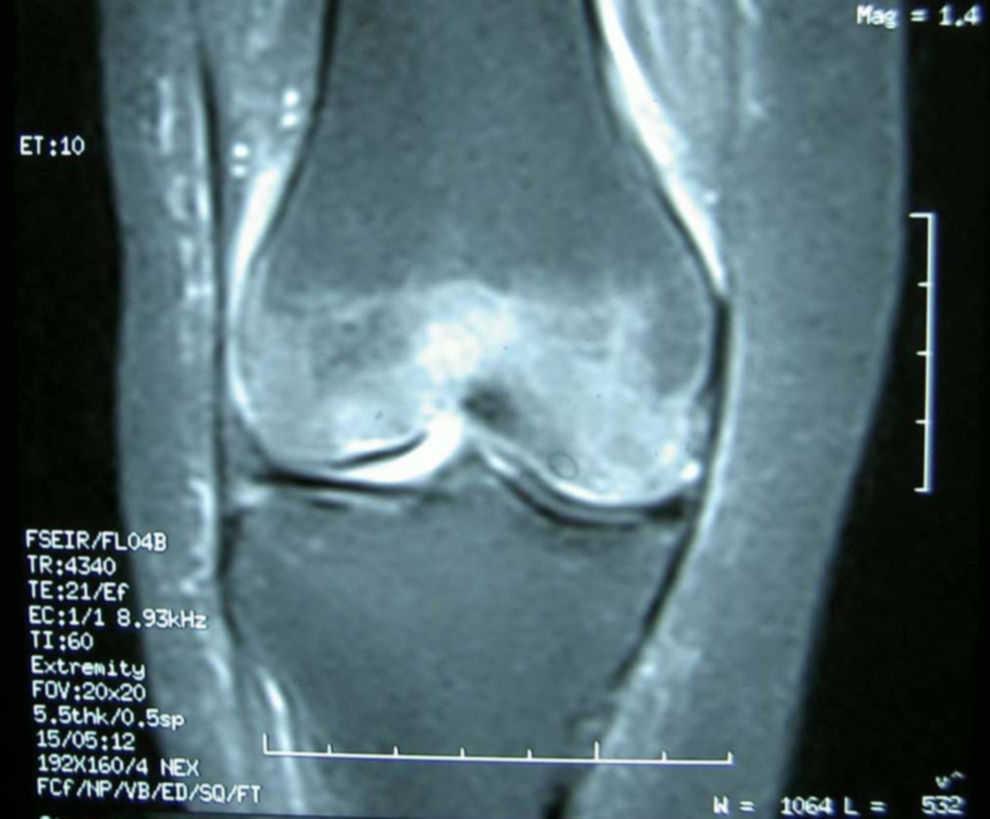

a. MR imaging indicated bone marrow edema of the proximal tibia, distal

Source: www.researchgate.net